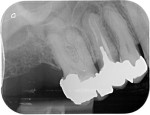

Root canal treatment can be a difficult procedure for the dentist to perform to the internal complexity of the canal system.

On the second appointment we do the same procedure with local anaesthetic and disinfect and prepare the canals, once we are happy with our preparation the canals are sealed with rubber points and a sealant into each canal. Radiographs may be taken to check our progress before sealing. A temporary restoration may be placed depending if the tooth requires further treatment.

Unfortunately root canal treated teeth are more prone to fracturing than unrestored teeth, a crown or inlay may be required although the dentist will discuss this with you prior to treatment commencing.

A follow up x-rays is normally taken a year after completion to ensure any areas of infection are healing.